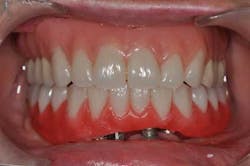

Fig. 14: Hybrid screw-retained mandibular prosthesis

Fig. 15a, b: Final result (removable complete denture on the maxillary)